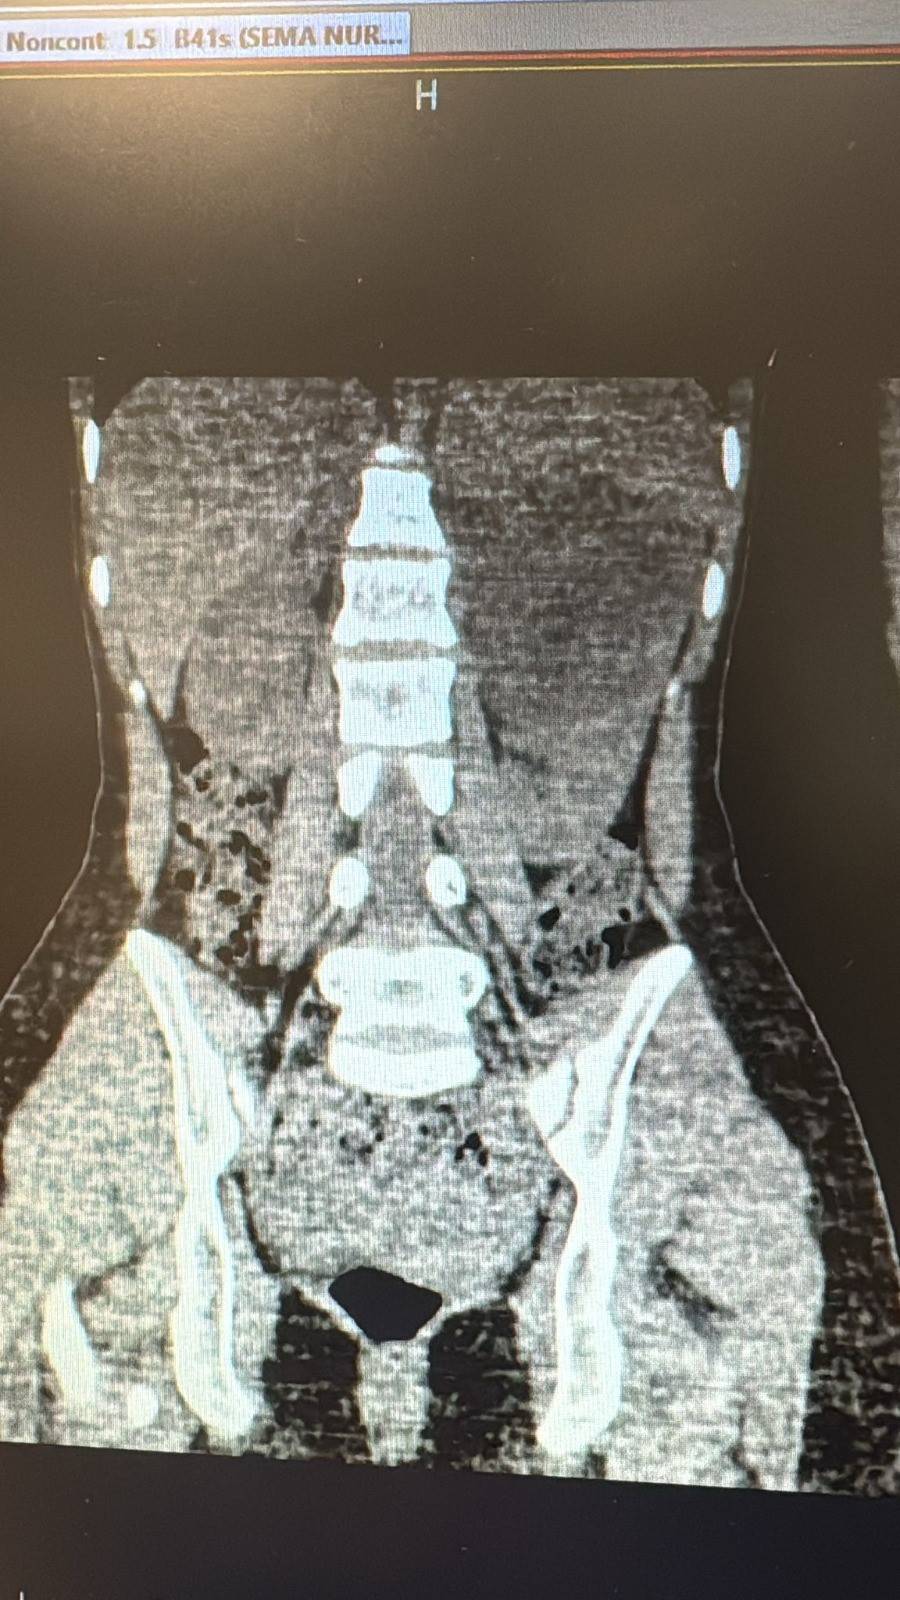

Şanlıurfa Viranşehir’de 10 Santimlik Böbrek Kisti Alındı

Şanlıurfa Viranşehir Devlet Hastanesi’nde, 18 yaşındaki bir hastanın sol böbreğinde tespit edilen yaklaşık 10 santimetre çapındaki kist, laparoskopik (kapalı) yöntemle başarıyla çıkarıldı.

Uzun süredir sol yan ağrısı şikâyeti bulunan kadın hasta, dış merkezde yapılan tetkiklerde sol böbrekten kaynaklanan, böbrek ve dalağı iterek komşu organlara yapışıklık gösteren büyük bir kist tespit edilmesi üzerine Viranşehir Devlet Hastanesi’ne sevk edildi.

Hastanede yapılan değerlendirmelerin ardından kistin cerrahi yöntemle alınmasına karar verildi. Üroloji kliniğinde gerçekleştirilen operasyonda, 10 santimetre boyutundaki böbrek kisti laparoskopik yöntemle, 2 adet 5 milimetre ve 1 adet 10 milimetrelik kesi kullanılarak çıkarıldı. Böylece hasta, açık cerrahiye gerek kalmadan tedavi edildi. Ameliyat sonrası takiplerinde herhangi bir komplikasyon gelişmeyen hasta, sağlığına kavuşarak taburcu edildi.